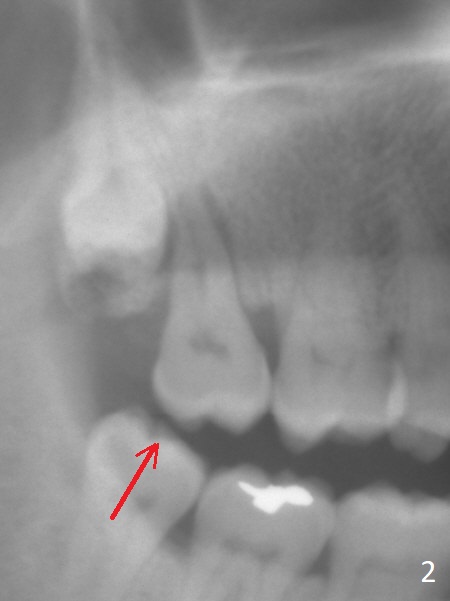

A 67-year-old man has pain associated with the tooth #2 with distal deep pockets (Fig.1), consistent with root fracture. The abnormal force may arise from the mesioangular lower 3rd molar (Fig.2 arrow). To avoid damage to the upper 3rd molar, osteotomy will be initiated obliquely with starter drill in the mesial slope of the socket (Fig.3 red). Once the starter drill makes a short entry, use 2 mm drill to change trajectory (Fig.4). Due to the uneven wall, an implant is expected to be placed distally by itself (Fig.5). The bone height is ~18 mm. If the patient agrees, remove the lower 3rd molar (Fig.5 black area).